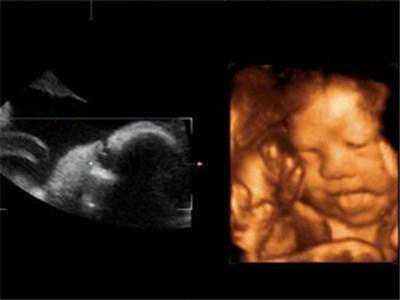

试管婴儿移植后如何保胎最佳?

试管婴儿移植问的最多的五大问题,答案都在这了!一、试管婴儿怎...